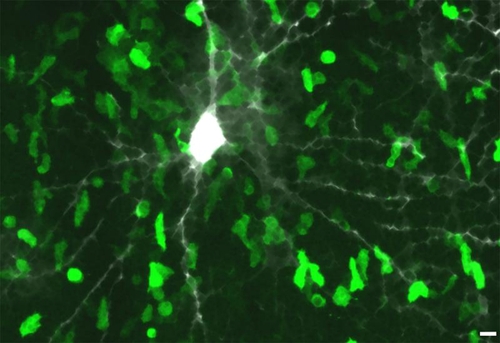

Durchbruch in der MS-Forschung? Zum Verständnis der Schädigung der grauen Hirnsubstanz

Bei der Multiplen Sklerose stand bisher die durch Immunzellen verursachte Schädigung der weißen Hirnsubstanz im Fokus der Forschung, obwohl man schon länger vermutet hatte, dass Symptome wie Fatigue oder kognitive Störungen auch auf eine Beteiligung der grauen Hirnsubstanz hinweisen. Forschende der Universitätsmedizin Göttingen haben nun ein Modell entwickelt, anhand dessen neue Krankheitsmechanismen entdeckt und Schädigungsprozesse der grauen Hirnsubstanz erstmals systematisch so erforscht werden können, dass sich in Zukunft geeignete therapeutische Gegenstrategien entwickeln lassen.

© Universitätsmedizin Göttingen